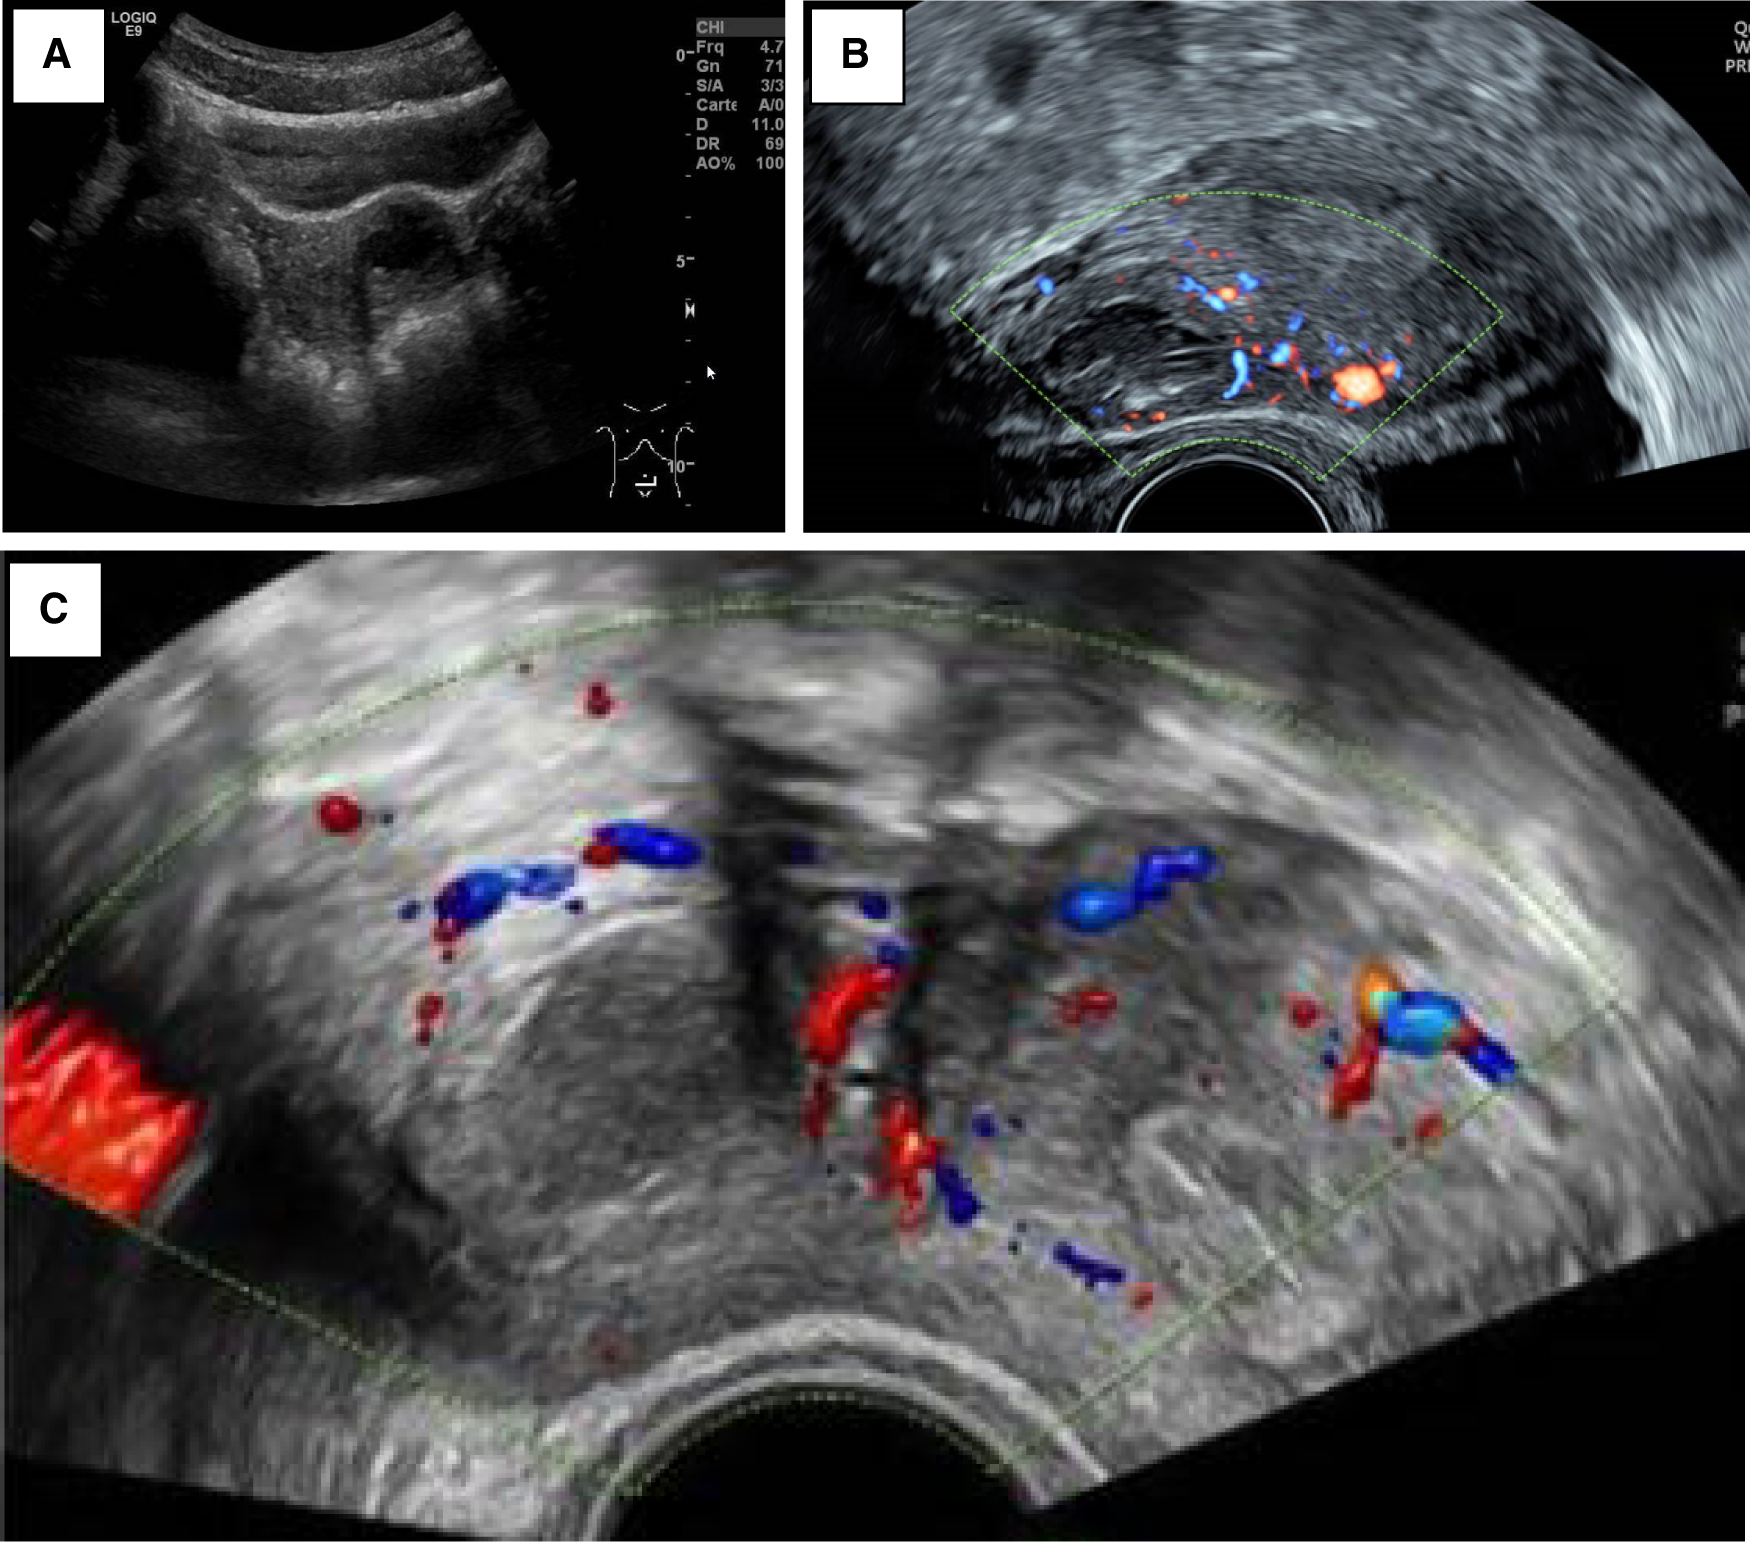

Severe dysmenorrhea (n = 5) and CPP (n = 4) were the most common presenting symptoms. As part of the clinical workup, the patients first underwent a pelvic ultrasound (Figure 1). A single lateralized intra-myometrial accessory cavity located under the insertion of the round ligament was found in all patients. The capsule of the lesion had the same echogenicity as the normal myometrium, and the content appeared as hypoechogenic.

Figure 1. (A) Patient 3_TAUS shows a left antero-fundic sub-serous mass of 3.8 cm × 3.6 cm. (B) Patient 4_axial plan of TVUS showing the right-lateralized mass separated from the normal uterine cavity by a thick myometrial wall. (C) Patient 5_axial echography showing a round right-lateralized mass with hypoechogenic content surrounded by a ring-shaped vascularized capsule.